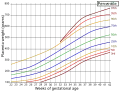

Immunological barrier